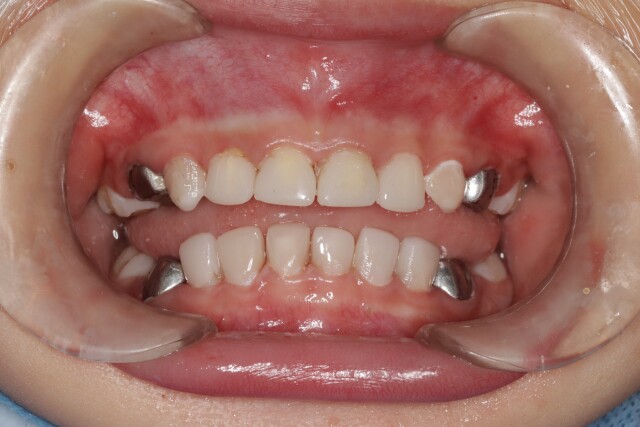

游弋第一时间对乐乐进行了口腔评估,在完善麻醉术前检查和评估后,为乐乐实施了全麻下患牙一次性舒适化治疗,包括龋齿充填、根管治疗、牙冠修复以及涂氟等治疗。3小时后,乐乐顺利完成治疗,乐乐妈妈也长舒了一口气:“原以为乐乐坏了这么多颗牙,可能需要跑医院很多趟,而且孩子对看牙极不配合,想想就头痛,现在好了,一次就全部解决了。”在医院观察4小时后,乐乐开心地跟妈妈回家了。

乐乐治疗后